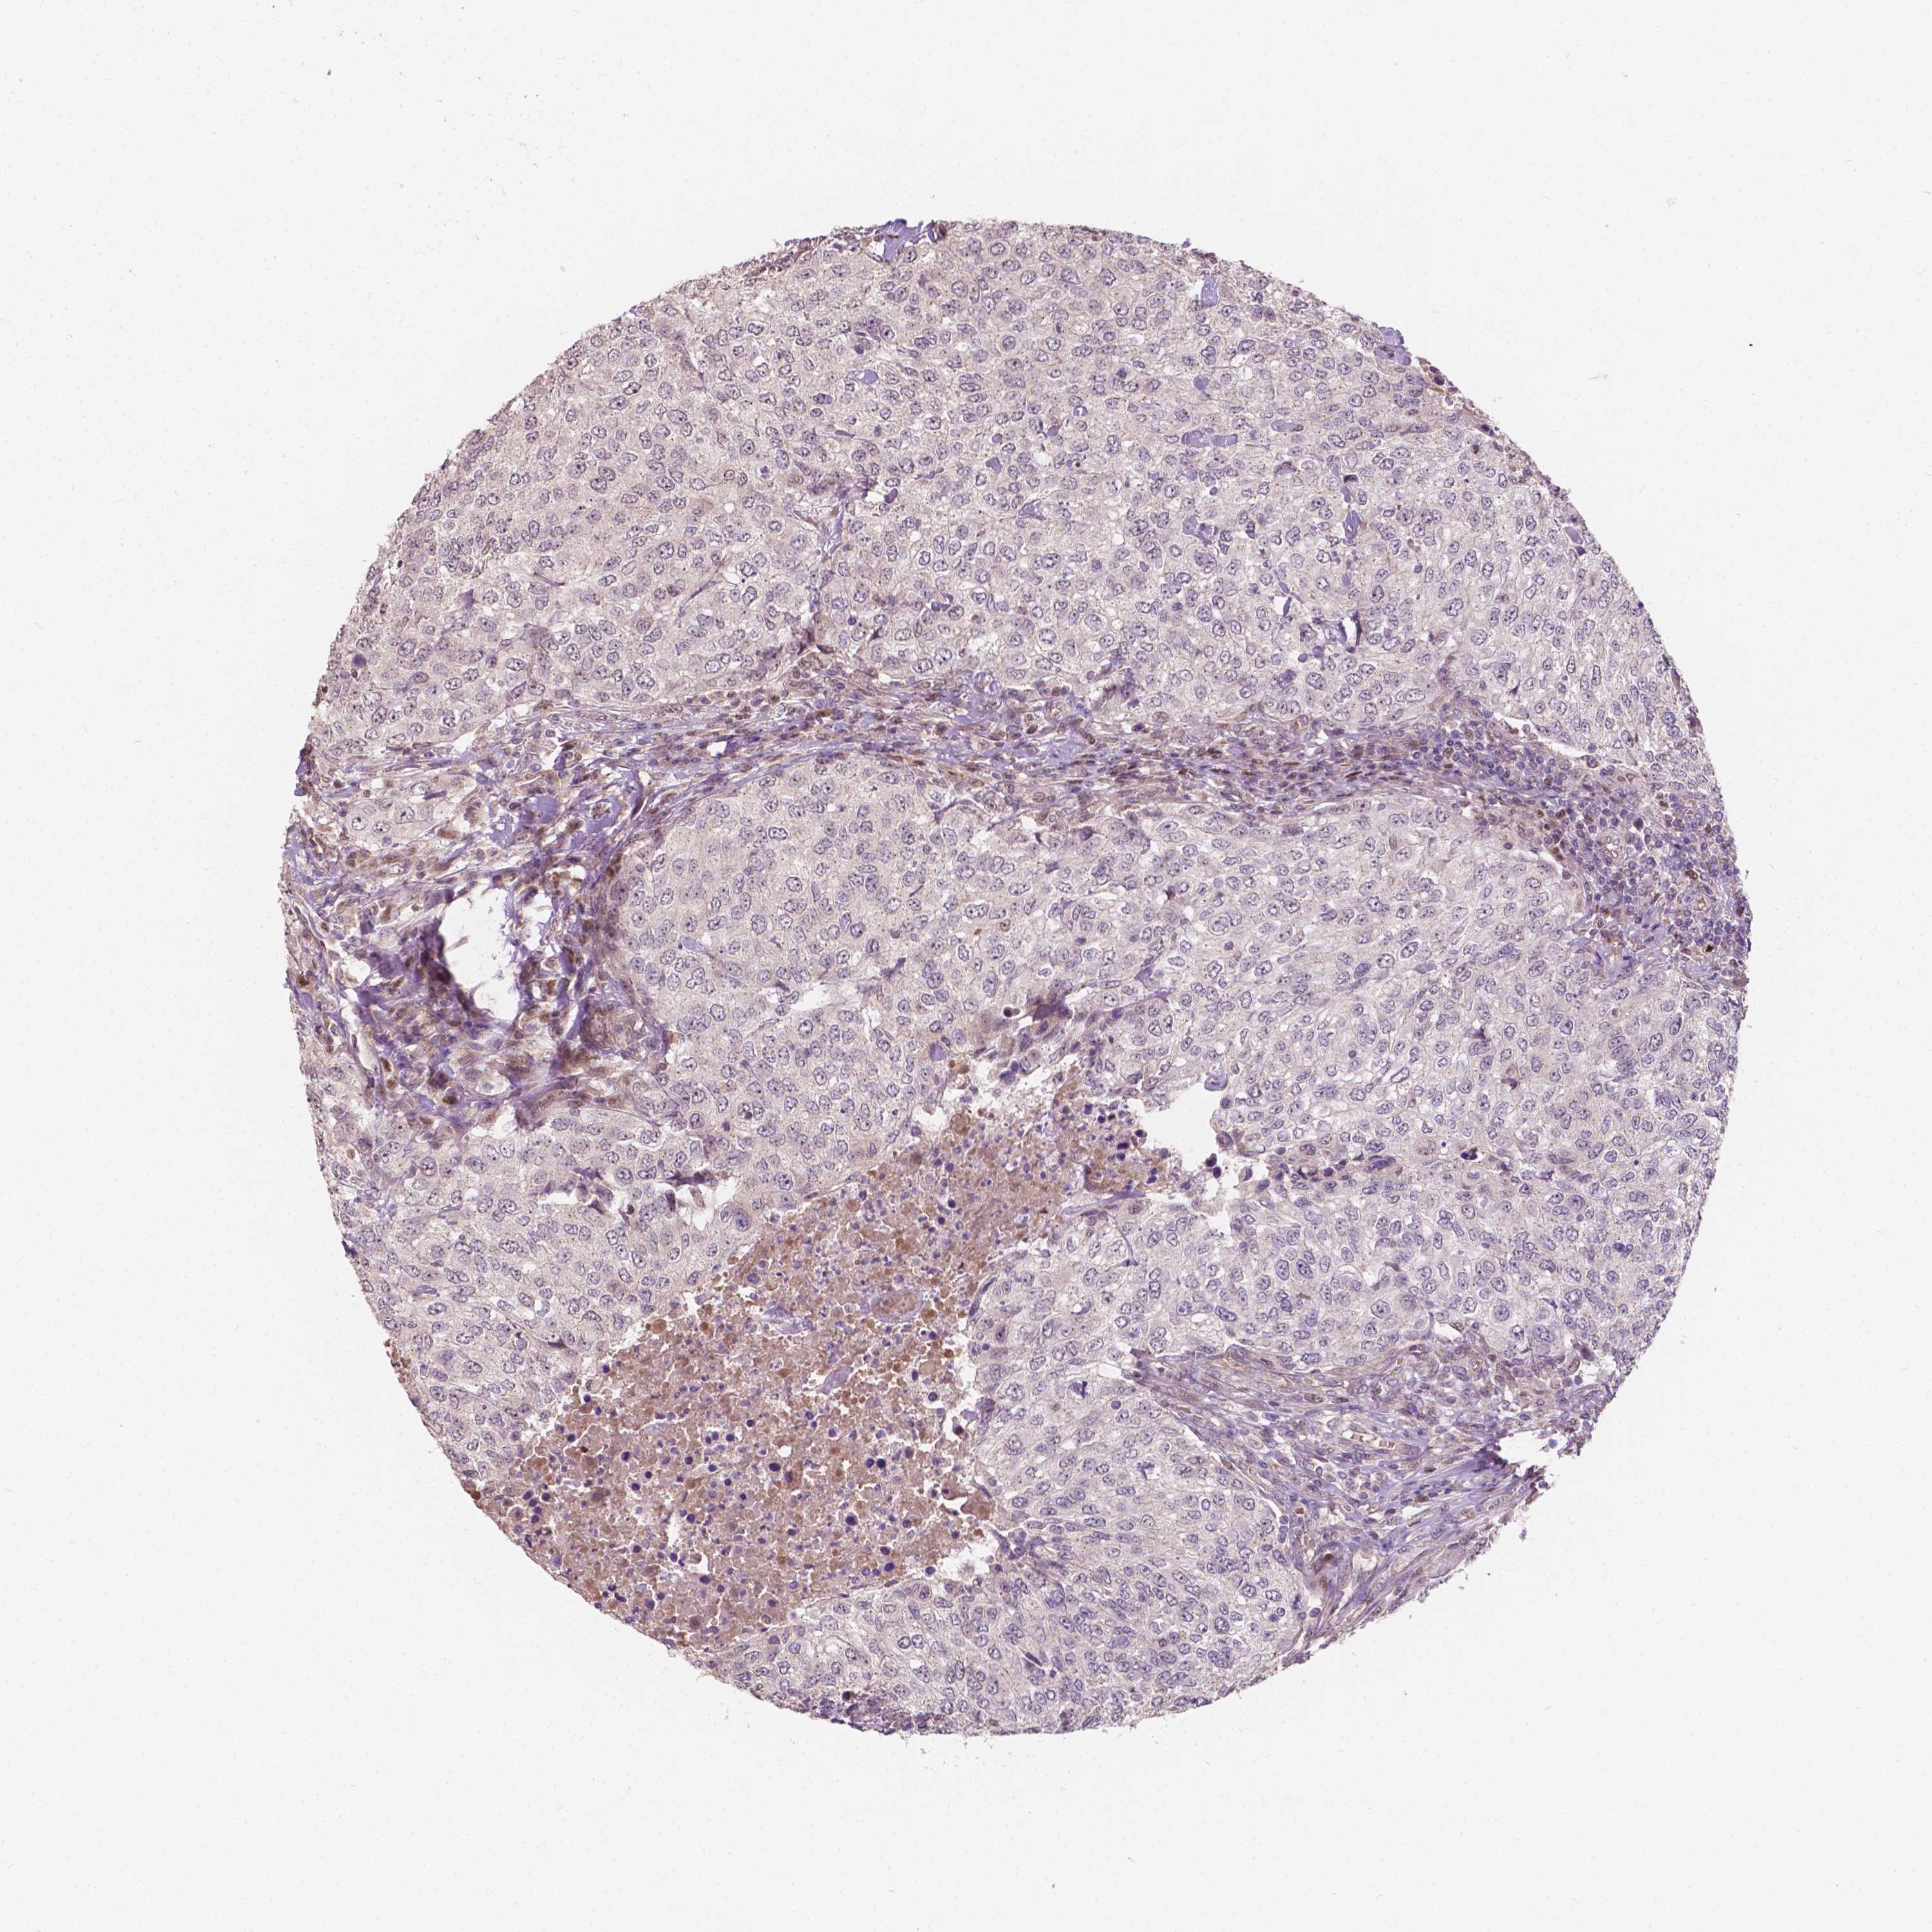

UROTHELIAL CANCER - Protein expressioni

A mouse-over function shows sample information and annotation data. Click on an image to view it in a full screen mode. Samples can be filtered based on level of antibody staining by selecting one or several of the following categories: high, medium, low and not detected. The assay and annotation is described here.

Note that samples used for immunohistochemistry by the Human Protein Atlas do not correspond to samples in the TCGA dataset.

Antibody stainingi

Antibody staining in the annotated cell types in the current human tissue is reported as not detected, low, medium, or high, based on conventional immunohistochemistry profiling in selected tissues. This score is based on the combination of the staining intensity and fraction of stained cells.

Each image is clickable and will lead to virtual microscopy that enables deeper exploration of all samples and also displays staining intensity scores, fraction scores and subcellular localization as well as patient and tissue information for each sample.

Antibody HPA020326

Staining

High

Medium

Low

Not detected

Intensity

Strong

Moderate

Weak

Negative

Quantity

>75%

75%-25%

<25%

None

Location

Nuclear

Cytoplasmic/membranous

Cytoplasmic/membranous,nuclear

Urothelial carcinoma, High grade

Urothelial carcinoma, NOS

Urothelial carcinoma, Low grade